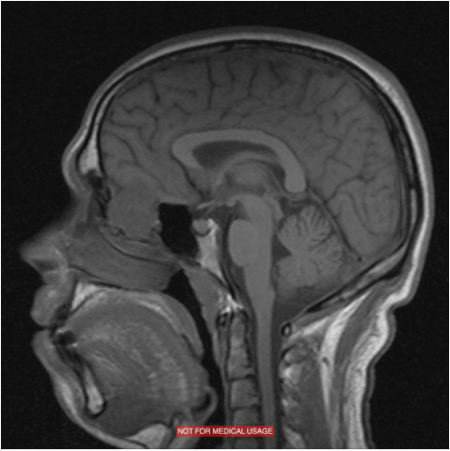

Las enfermedades de la base del cráneo requieren cirujanos expertos y procedimientos altamente específicos, considerando las dificultades anatómicas de la región y las importantes estructuras allí localizadas. En la Unidad Alergo·Rino tenemos una dilatada experiencia en el tratamiento de enfermedades tumorales y malformaciones que afectan a la base del cráneo. Somos expertos en el abordaje endoscópico mínimamente invasivo.

La Unidad dispone de un sistema de Navegación con imágenes de alta definición que aporta datos anatómicos en tres dimensiones para mejorar la orientación dentro del campo quirúrgico ayudando en los distintos pasos quirúrgicos y mejorando la seguridad. En nuestra Unidad tratamos todas las lesiones que afectan la base de cráneo tales como: tumores malignos de senos paranasales, angiofibroma juvenil, adenomas hipofisarios, cordomas, meningiomas, quistes de Rathke, y lesiones de la unión craneo-vertebral.